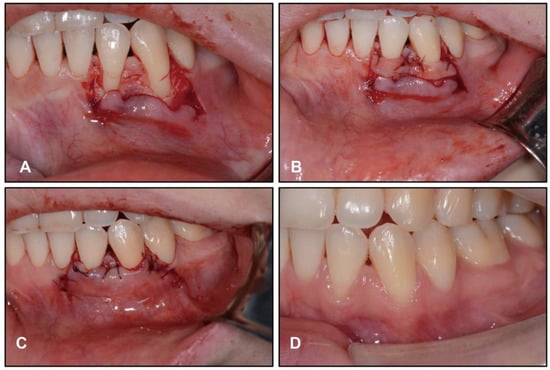

2.4. Treatment Progress